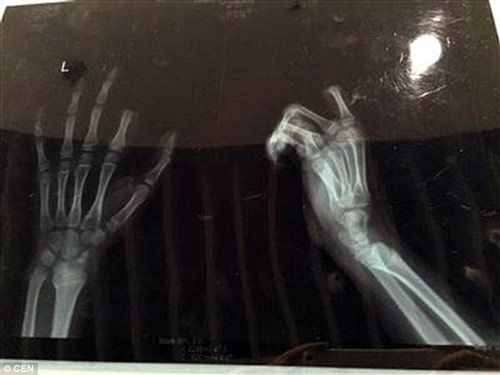

Dailymail đưa tin, vụ việc này xảy ra hôm 5/3 vừa qua tại thành phố Tô Châu, tỉnh Giang Tô, Trung Quốc. Cậu bé Peng (11 tuổi) đã được bố mẹ đưa tới bệnh viện cấp cứu trong tình trạng bị đứt lìa 2 đốt trên của ngón tay trỏ bên trái, chảy máu nhiều.

Do được đưa vào viện kịp thời, sau 3 giờ phẫu thuật, các bác sỹ tại bệnh viện ở Tô Châu đã nối tạm thời ngón trỏ bị đứt lìa cho cậu bé. Tuy ca phẫu thuật thành công nhưng rất có thể ngón tay trỏ của Peng không thể cử động tốt như trước.

Bác sỹ Zhou Rong, một trong những người trực tiếp phẫu thuật cho Peng cho biết: "Hiện ngón tay đã được kết nối tạm thời nhưng chúng tôi vẫn phải theo dõi thêm. Nếu cậu bé cử động quá nhiều sẽ gây ra tình trạng nghẽn mạch dẫn đến việc ngón tay có nguy cơ hoại tử hoàn toàn".